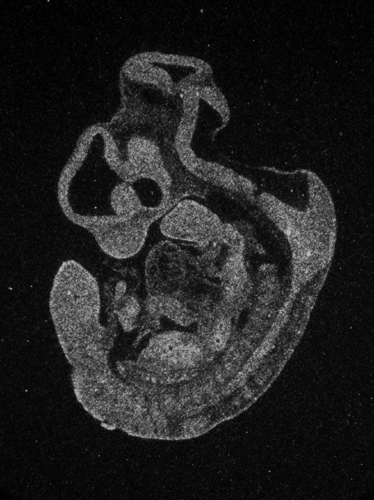

Specimen

g02349 E11.5:

embryonic day 11.5

Genetic Background:

C57BL/6

Age:

Sex:

Not Specified

Type:

section

Fixation:

4% Paraformaldehyde

Embedding:

Cryosection